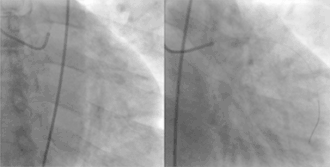

Coronary angiography and angioplasty in acute myocardial infarction (left: RCA closed, right: RCA successfully dilated)